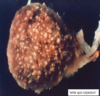

Reptilian Cryptosporidiosis

C.saurophilum

Wasting syndrome